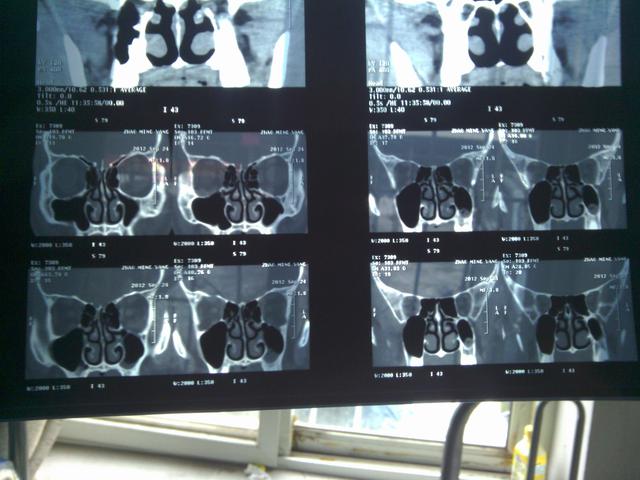

诊断

临床症状喷嚏、清水样涕、鼻塞、鼻痒等症状出现2项以上(含2项),每天症状持续或累计在1小时以上。可伴有眼痒、结膜充血等眼部症状。体征常见鼻黏膜苍白、水肿、鼻腔水样分泌物。变应原皮肤点刺试验阳性,和/或血清特异性IgE阳性,必要时可行鼻激发试验。

4.外科治疗

其适应证为经药物或免疫治疗鼻塞症状无改善,有明显体征,影响生活质量;鼻腔有明显的解剖学变异,伴有功能障碍;合并慢性鼻-鼻窦炎、鼻息肉,药物治疗无效。外科治疗不作为常规治疗变应性鼻炎的方法。